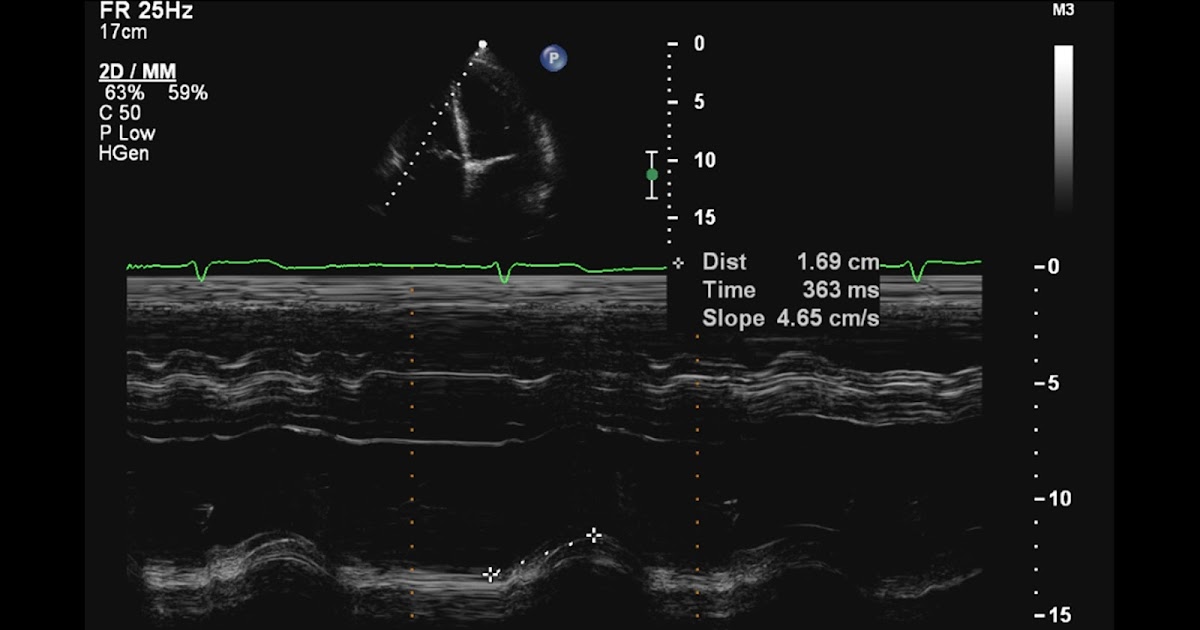

Tricuspid annular plane systolic excursion (TAPSE) in Mmode obtained

Tricuspid annular plane systolic excursion (TAPSE) in Mmode obtained Tapse Echo Adalah It is considered among the most reliable tools to measure or estimate the ejection fraction of the right ventricle (rv), cardiac output and diastolic function. Selamat malam, terima kasih telah bertanya di alodokter.tricuspid annular plane systolic excursionatau tapse, adalah salah. Rv dilation may be due to: A ratio of <0.31mm/mmhg was predictive of patients having a significantly worse prognosis than. Tapse Echo Adalah.